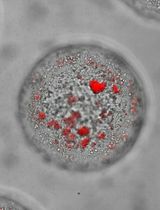

Stain the slides in TRAP Staining Solution for 30-45 min in an oven at 37°C. Monitor the color change every 15 min until the TRAP-positive area turns red.

Analyze osteoclast differentiation in TRAP stained slides

Count the occurrence of TRAP positive cells at the tumor and bone interface.

Calculate the average occurrence of TRAP positive cells at the tumor and bone interface.

Show representative images with higher resolution as desired (Figure 3).

Figure 3. TRAP staining in 5-week tibial tumors. Shown are representative images of 2.5× (A, B), 10× (C), and 40× (D) magnifications of a PC-3 tibial tumor sample. Scale bars in A-B: 500 µm. Scale bar in C: 100 µm. Scale bar in D: 50 µm. T, tumor tissue. B, bone tissue. BM, bone marrow. M, muscle tissue. The lengths of tumor and bone interface were calculated in B using NDP.view2.